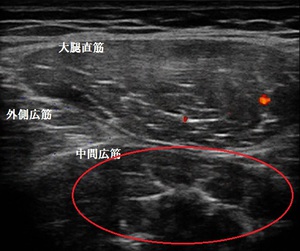

右大腿部 超音波長軸像 右同部 短軸像

鶴ヶ島市若葉 30代男性会社員。 もも(大腿部)の痛み、打撲。

超音波検査をしたところ、中間広筋が打撲により挫滅し内出血と浮腫が認められました(左右画像の

赤丸内)。